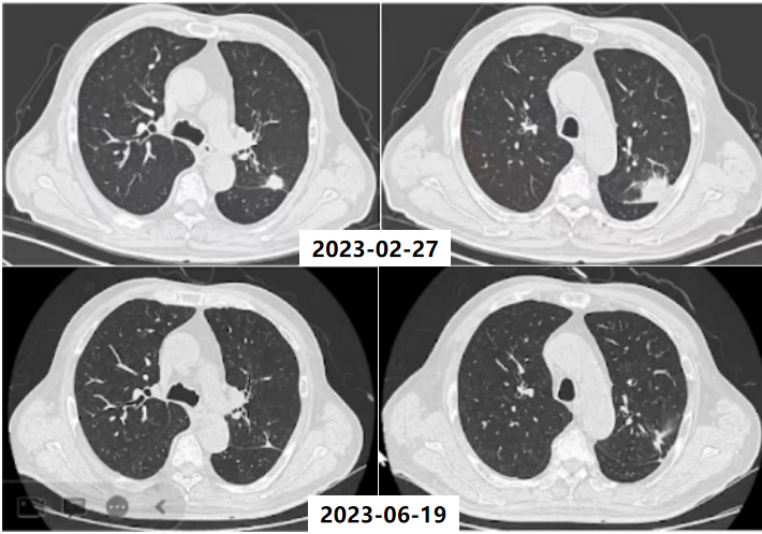

Lemierre综合征(LS)是以法国医生Andre Lemierre的名字命名,他在1936年报告了20例由口咽感染引起的厌氧败血症。(1)流行病学:在抗生素广泛应用的年代,LS的发病率急剧下降。自70年代后期口腔感染中经验性抗生素的使用减少,报告的病例数量稳步上升,被称为“被遗忘又重现的疾病”,发病率为每年1/10000000,通常为青少年和年轻人,即使使用适当的抗生素和治疗,报道死亡率也在5%~18%之间。(2)致病菌:导致LS的致病菌通常为坏死梭杆菌(>70%),它是严格的专性厌氧革兰氏阴性杆菌。(3)病理生理:首先由于细菌、病毒致咽部黏膜损伤,在此基础上出现坏死梭杆菌的二重感染:①感染至咽外侧间隙和颈部软组织,引起外源性压迫,出现炎症、水肿;②内源性闭塞,出现血管内凝血。在上述基础上发生颈内静脉脓毒性血栓形成;感染性栓子从任何一条静脉播散,都可能导致肺、胸膜、关节、骨骼、肌肉、肝、脾、肾等多处器官受累。(4)临床特征:①口咽感染;②颈内静脉血栓性静脉炎感染延伸至颈部旁间隙;③脓毒性栓子播散引起菌血症、脓毒性休克。(5)诊断:①血培养:培养时间需要6~8天,阳性率低;②分子生物学方法:快速且准确,有助于早期诊断;③BALF、m-ROSE、NGS等。LS的Sinave诊断标准:①口咽部的原发感染;②脓毒败血症;③颈内静脉感染性栓塞;④远处脏器转移性化脓灶。(6)治疗:①抗菌药物治疗:碳青霉烯类、β-内酰胺/β-内酰胺酶抑制剂联合甲硝唑是治疗LS最有效的药物。②抗凝治疗。③外科治疗。(1)定义:齿垢密螺旋体是一种螺旋形的革兰氏阴性厌氧菌,属解糖密螺旋体,与口腔以及牙周感染性疾病密切相关。(2)流行病学:关于齿垢密螺旋体,近4年来仅有寥寥数篇报道,极为罕见。(3)易患人群:长期卧床、生活无法自理导致口腔卫生较差、牙周状况不理想、免疫功能低下的老年人。(4)临床症状:多为非特异性症状,可有吸入性肺炎的一系列临床表现,如咳嗽、咳痰、甚至咯血,也可有畏寒、发热等。(6)治疗:目前仍按照密螺旋体属中常见人致病螺旋体进行治疗,首选为青霉素,其他如半合成青霉素、四环素类等药物亦有较好效果。患者男性,72岁。主诉:间断咳痰、咯血1月半余,发现肺结节1月余。患者2023年2月中旬无明显诱因出现间断咳痰,咳白黄痰,痰中带血,每天5~6次,无发热,无胸痛等不适,后出现咯鲜血,咯绿豆大小血块,4~5次/天,就诊于当地医院,胸部CT提示左肺上叶占位,予莫西沙星抗感染治疗约1周后症状好转,后就诊于我院。入科后,予患者支气管镜下肺泡灌洗并将BALF送检mNGS,结果回报检出齿垢密螺旋体(序列数36条)。予哌拉西林他唑巴坦4.5 g q8h+米诺环素100 mg q12h抗感染,调整治疗方案为美罗培南1 g q8h,后期仅采用替加环素50 mg q12h治疗。抗感染治疗后,患者左肺上叶结节明显缩小。非典型病原体是一种细胞内或细胞旁的细菌病原体,无法通过革兰氏染色和传统培养基进行识别,对β-内酰胺具有内在耐药性。2022年Microorganisms杂志发表的综述显示,在CAP病因中,非典型病原体占15%,这其中,肺炎支原体位居首位,其次是肺炎衣原体,然后是嗜肺军团菌以及鹦鹉热衣原体等。1976年夏天宾夕法尼亚州费城Bellevue-Stratford酒店举行的为期3天的美国退伍军人协会年度大会上,嗜肺军团菌感染首次被发现。(1)流行病学:既往军团菌肺炎的病死率可达10%~15%,院内感染死亡率可达25%~50%。随着喹诺酮类药物的临床应用,该病病死率有所下降。该病发病具有季节性,全年均可发生,以6~10月发病最多。(2)致病菌:军团菌肺炎的致病菌通常为嗜肺军团菌血清型1,约占90%,是一种需氧革兰氏阴性杆菌,细胞内寄生菌,双相生存周期。(3)传播途径:军团菌广泛存在于自然界中,尤其是温暖潮湿的环境,如人工冷水、天然水源、潮湿土壤等。军团菌感染多通过吸入受污染的人造水源(如淋浴、管道、空调系统等)产生的含军团菌气溶胶。(4)易患人群:>50岁、吸烟、免疫抑制(尤其是细胞免疫抑制)、合并慢性心肺疾病等。(5)影像学表现:肺部变化通常为单侧,主要局限于下叶,但也可能出现在两侧,包括肺部的上下部分;肺部的炎症变化可表现为3种类型的浸润——肺泡型、间质型和局灶型。军团菌肺炎的胸部X线片和CT最具特征的表现是不规则形状的肺组织大面积固结,靠近肋和/或水平胸膜,有空气支气管造影征象和局灶性肺泡-间质磨玻璃样混浊。